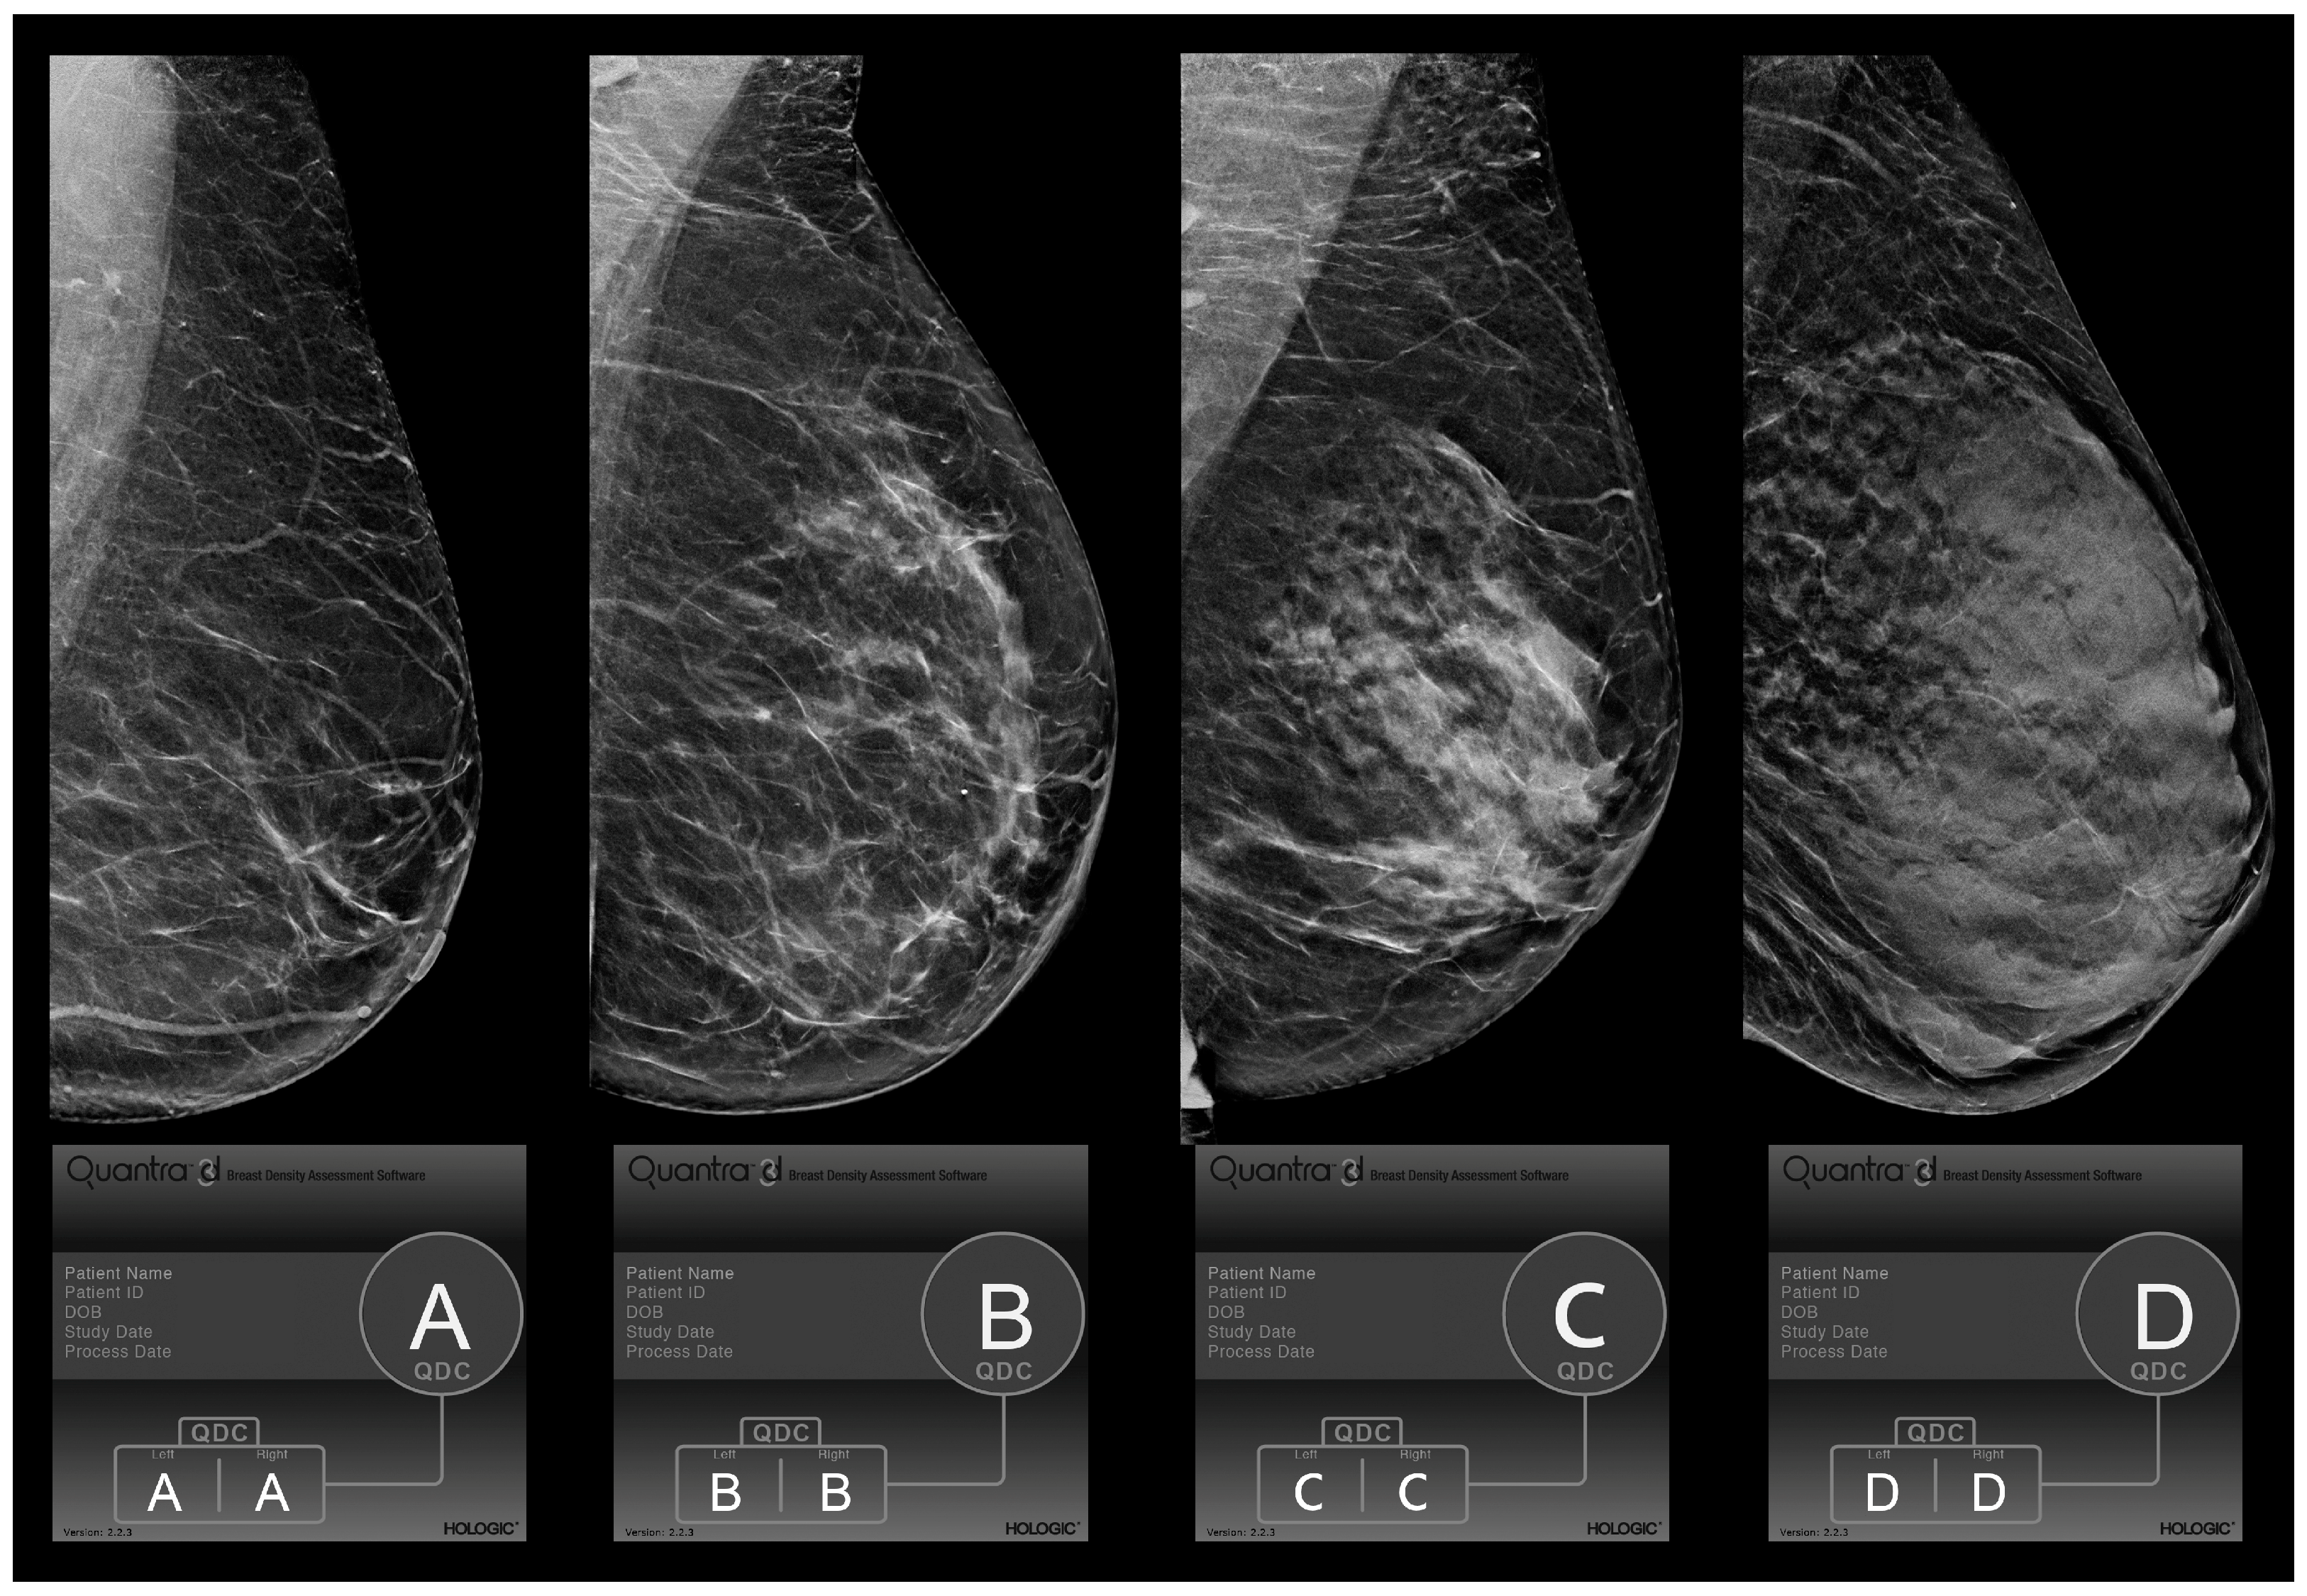

The 4th edition of BI-RADS identified four categories based on the percentage of fibroglandular tissue present on the whole parenchymal area (category 1: <25%; category 2: 25–50%; category 3: 50–75%; category 4: >75%) [16]. The 5th edition of BI-RADS (Figure 1) [17] redefined this classification, giving more relevance to the qualitative analysis, so that even the presence of isolated areas of high breast density could increase the score due to the masking effect of a lesion. Specifically, by shifting the target from tissue percentage to parenchymal density, the new classification became more subjective, and the visual assessments of the BI-RADS categories showed a heterogeneous level of agreement between readers that varied from “slight” to “almost perfect”, as reported in previously published papers [18,19]. This discrepancy persisted due to many reasons, which included differences in the study populations, the reader’s level of experience, and the methods used in the study [20]. To support the analysis and to reduce the inter-reader variability, existing or new software has been upgraded to carry out an automatic assessment of breast density by analyzing mammographic images with machine-learning procedures, focusing on the distribution pattern of breast tissue rather than breast volumetric density alone.

Figure 1.

BI-RADS 5th Edition Quantra density categories (QDC). Evaluation of breast density categories performed by the Quantra softare (version 2.2.3) on digital breast tomosynthesis images according to BI-RADS 5th Edition. The lower boxes report the results of the Quantra evaluation for each breast and the final breast density assigned based on the denser breast. In these cases, since left and right breasts received the same evaluation, we showed only the left breast in medio-lateral-oblique (MLO) projection. Category A: almost entirely fat; category B: scattered fibroglandular densities; category C: heterogeneously dense; and category D: extremely dense.